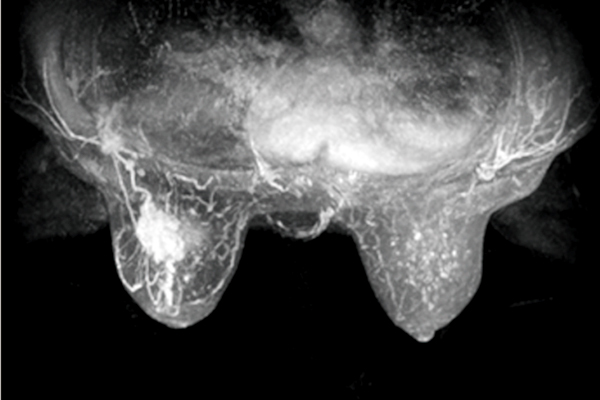

視野大,可使雙側(cè)乳腺、胸壁和腋下淋巴組織同時完整呈現(xiàn),適合不同乳腺大小的受檢者。